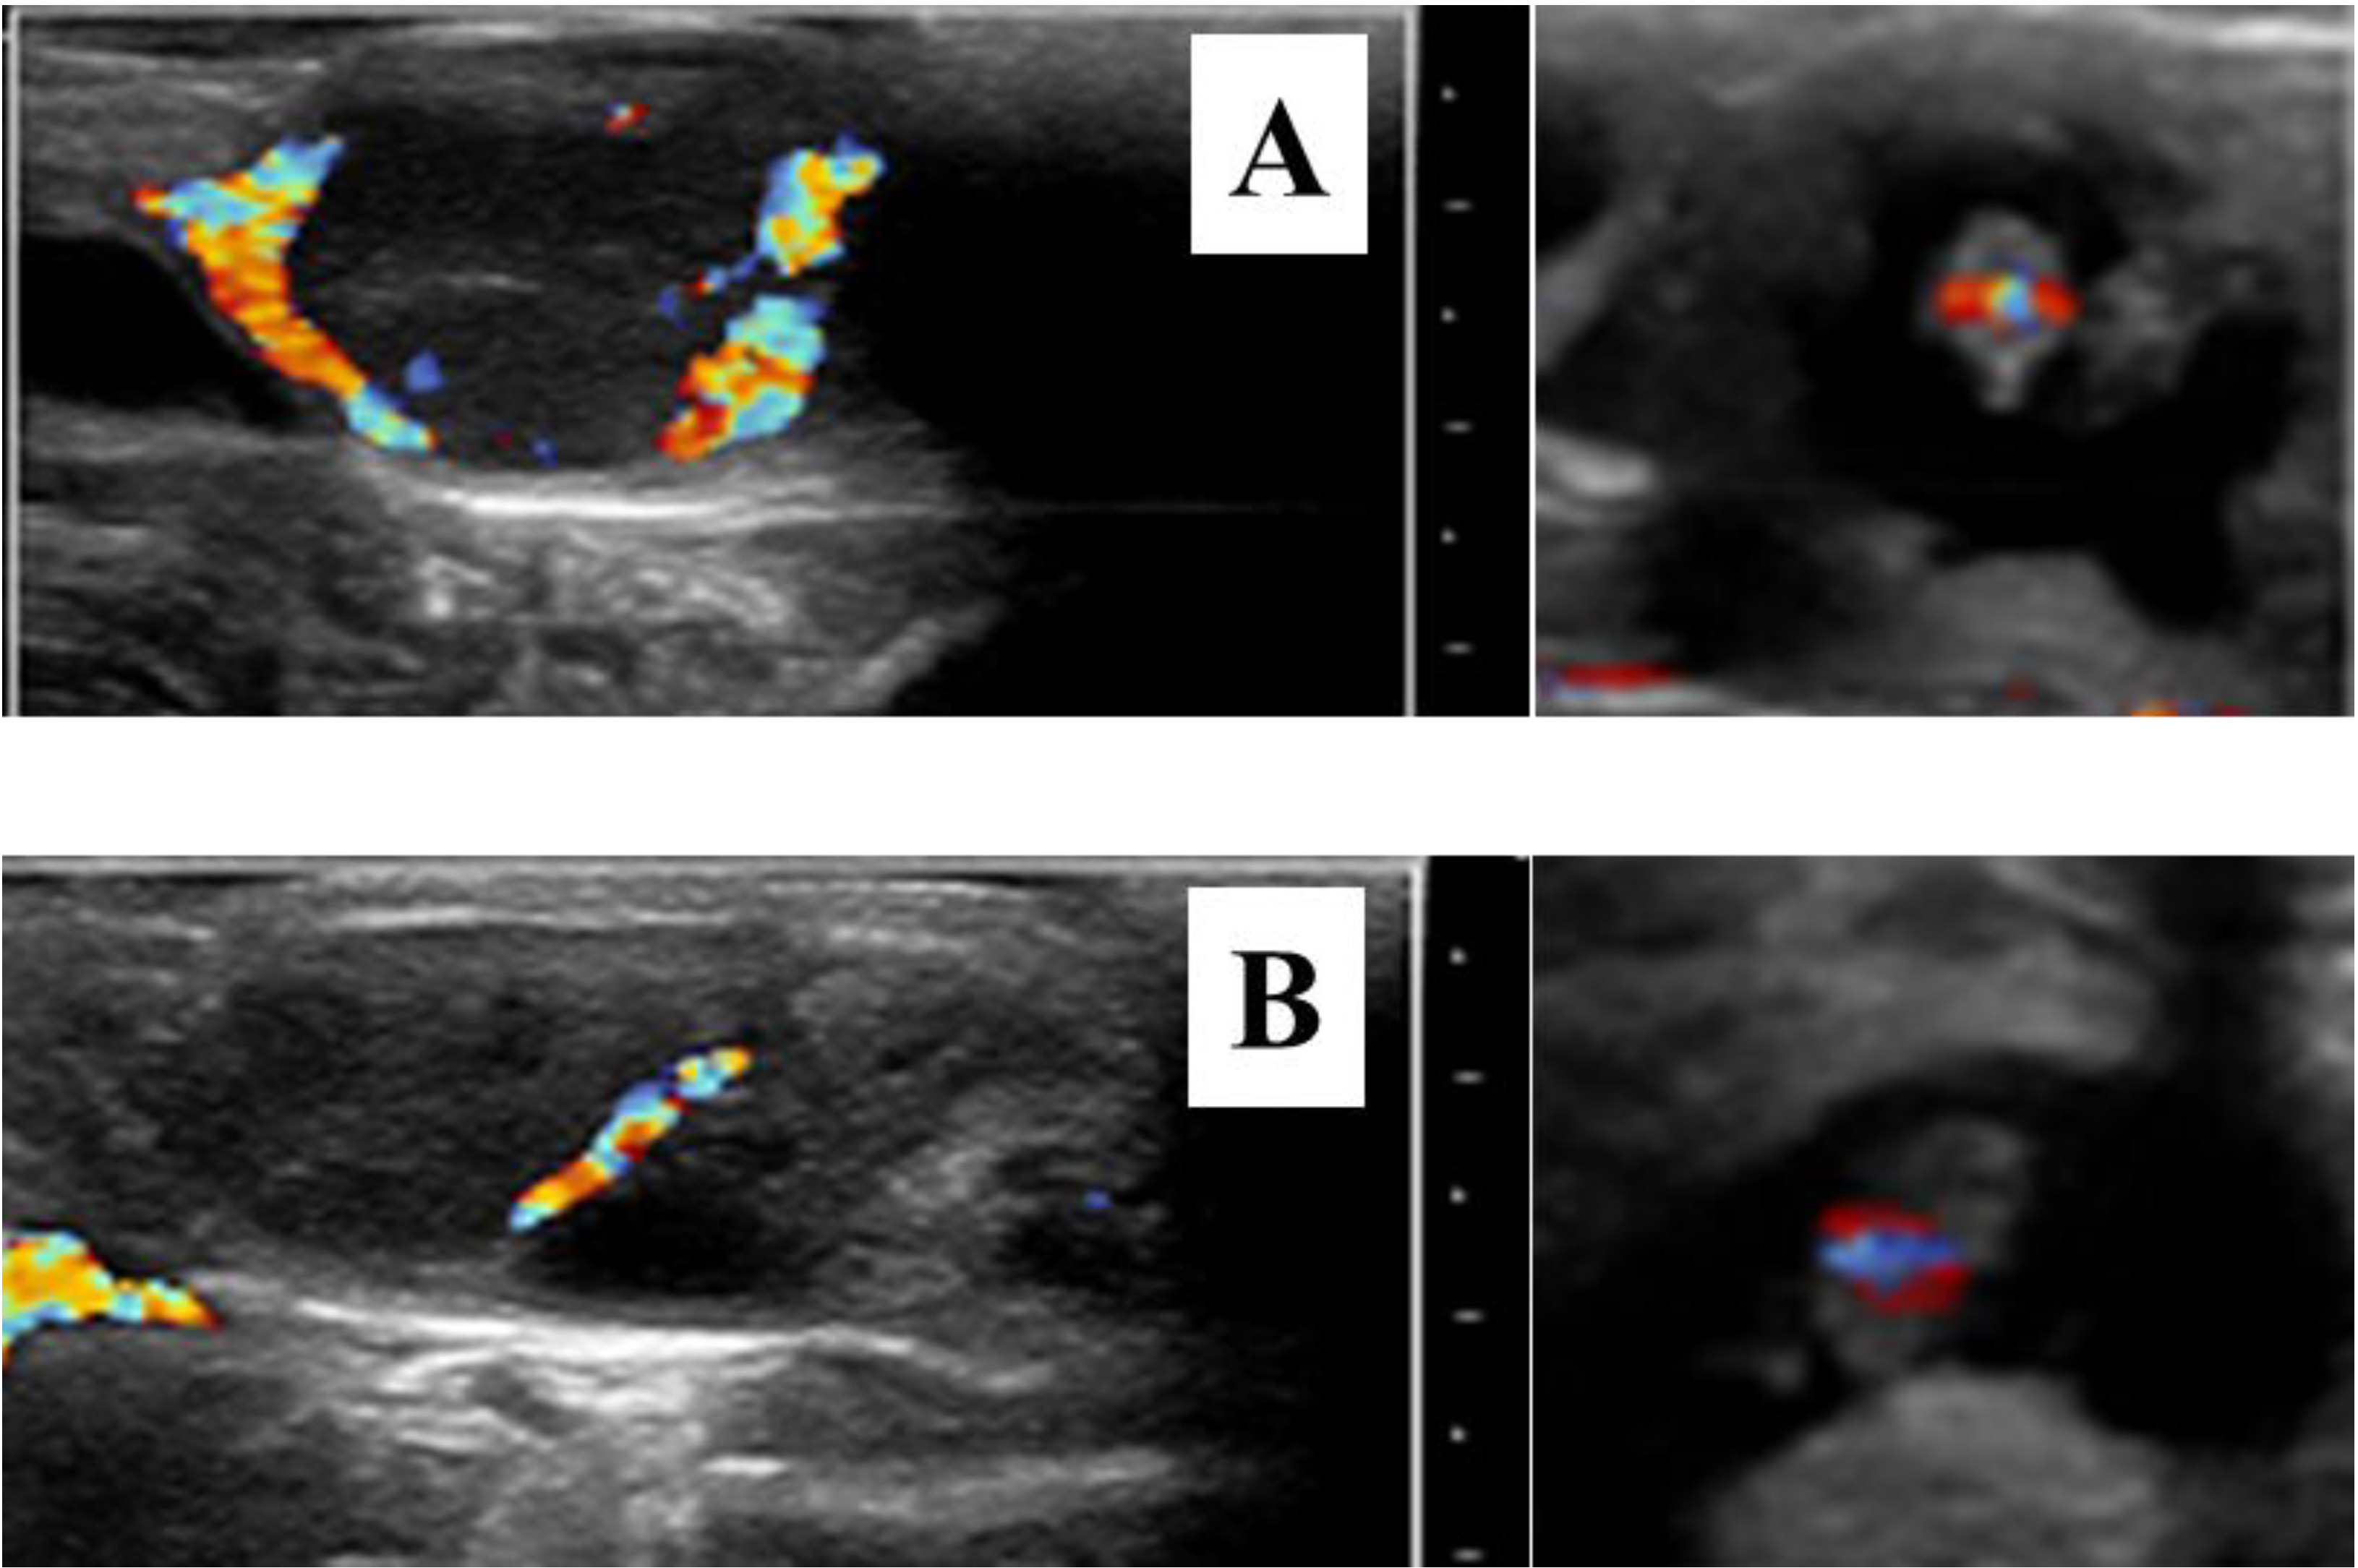

Numerous mechanisms are involved in the formation and regulation of luteal structures [31,32]. So, we can expect that the function of the CL is influenced by many factors. For example, poor luteal activity has been associated with the intense metabolism and steroid hormone clearance of high milk production [33,34]. Heat stress is also a main factor impairing the CL function [35,36,37]. Luteal deficiency, therefore, is not due to a single etiology, and an etiologic diagnosis may be difficult or impossible to establish in routine clinical practice. Irrespective of its origin, the diagnosis of sub-luteal function can be performed clinically on the basis of plasma or milk P4 concentrations. Post-ovulatory increase in plasma P4 concentrations is strongly correlated with pregnancy success [38], while advanced (<7 days) or delayed (>11 days) onset of luteal activity post-AI has been associated with a decreased pregnancy rate (9.3 and 12.1%, respectively) when compared to the 7–11 days interval [39]. Eventually, low plasma P4 concentration during the late embryonic period has been related to pregnancy loss [40,41,42]. However, it is difficult to establish a reliable cut-off value for predicting pregnancy loss. It seems that high plasma P4 concentrations are a more useful predictor of pregnancy maintenance than low P4 concentrations are for predicting pregnancy loss [21]. In this context, sequential ovarian brightness (B)-mode ultrasonography plus plasma P4 measurements from AI to pregnancy diagnosis (day 32 post-AI) have proven to be useful tools in diagnosing luteal deficiency [8]. Or better, color-flow Doppler ultrasonography could be used to monitor appropriate luteal vascularization at the time of pregnancy diagnosis (Figure 1). Luteal blood flow, a strong indicator of luteal function, may provide additional information on luteal physiology compared to plasma P4 measurements alone [43,44,45]. Doppler ultrasonography is already used at the time of embryo transfer for selection of recipients [46,47,48]. However, the relationship of CL blood flow with pregnancy maintenance or pregnancy loss has been scarcely studied during the late embryonic period. A positive correlation between CL blood flow and plasma P4 concentrations has been reported in pregnant cows up to day 40 of gestation [49]. Normal and low luteal vascular perfusions shown in Figure 1 are just one example to be confirmed in extensive studies. Doppler blood flow studies should provide significant information about luteal deficiency during the late embryonic period and pregnancy loss and its treatments.

Figure 1. Color-flow sonograms of corpora lutea and their corresponding 30-day embryos showing normal (A) and low luteal vascular perfusion (B). The apparent luteal vascular decrease in (B) compared to that of (A) was associated with pregnancy loss 14 days later. All images were selected on the basis of maximal vascular perfusion from real-time video clips. Bar spacing: 10 mm.